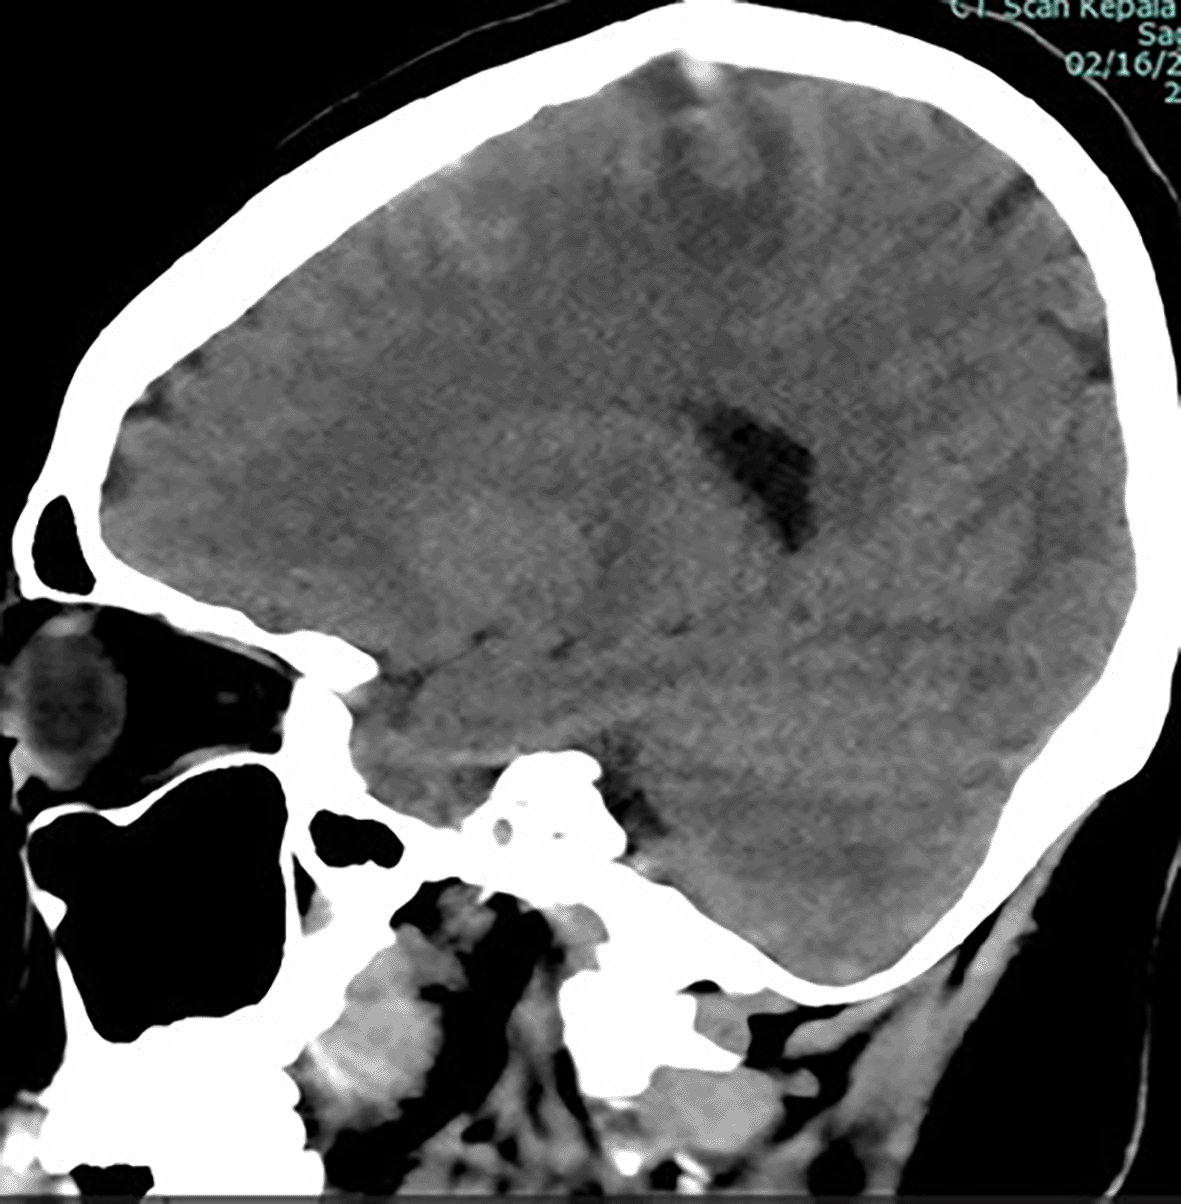

The patient in the ICU remained conscious (E4V5M6) but experienced another seizure. Therapy was administered as a loading dose of mannitol at 1 g/kg body weight, followed by a maintenance dose of 0.5 mg/kg four times daily, continuous magnesium sulfate at 2-3 mg/kg/hour, citicoline at 500 mg three times daily, and sedation with dexmedetomidine at 0.5-0.7 mcg/kg/hour. The patient exhibited clinical and hemodynamic enhancement. On the subsequent day (ICU H-3), the patient reiterated complaints of intense headache and agitation (E3V5M6), which were succeeded by seizures and diminished consciousness. A neurological assessment revealed left hemiparesis, with right/left motor strength recorded at 5-5/4-4, and no nuchal rigidity was observed. A CT scan of the head revealed a “Dens sign” alongside intracranial hemorrhage (ICH) encircled by considerable edema in the superior sagittal sinus region, accompanied by subarachnoid hemorrhage. Nimodipine at a dosage of 6x60 mg and a hypertonic saline loading dose of 3 mg/kg, subsequently followed by 1 mg/kg body weight every 8 hours, were administered. The left side limbs exhibited a decline in strength to 5-5/2-2, accompanied by diminished motor function in the right side limbs (4-4/2-2). The CT scan of the head without contrast (NCCT, Figure 1) prompted a consultation with the neurology division, followed by a D-dimer test yielding a result of 4870 ng/ml. An MRI and MRV of the head revealed a hemorrhagic venous infarct in the right-left parietal lobe (dominant right, volume approximately 15.5 cm), accompanied by perifocal edema that displaced the right-left lateral ventricle inferiorly, resulting in subfalcine herniation to the left side due to thrombosis with anteromedial occlusion of the superior sagittal sinus ( Figures 2-3). Anticoagulant therapy commences with an initial dose of 5000 IU of low molecular weight heparin (LMWH), followed by a maintenance dose of 1.8 IU/kg body weight, and a consultation with the neurosurgery division for decompression craniectomy.

ICH is seen from rupture of the superior sagittal vein.

The lesion produced significant local mass effect with effacement of the surrounding sulcus and left subfalcine herniation (3.8 mm).